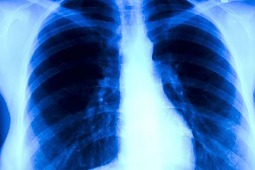

Zaburzenia w ekspresji aktywiny obserwowane są w wielu nowotworach złośliwych. Część z dotychczas przeprowadzonych badań informowała, iż aktywina A odgrywa istotną rolę w patogenezie złośliwego międzybłoniaka opłucnej. Mir Alireza Hoda i wsp. zaprojektowali badanie mające na celu określenie przydatności oceny stężenia aktywiny A jako markera rozwijającego się złośliwego międzybłoniaka opłucnej. Wyniki badania opublikowano na łamach czasopisma European Journal of Cancer.